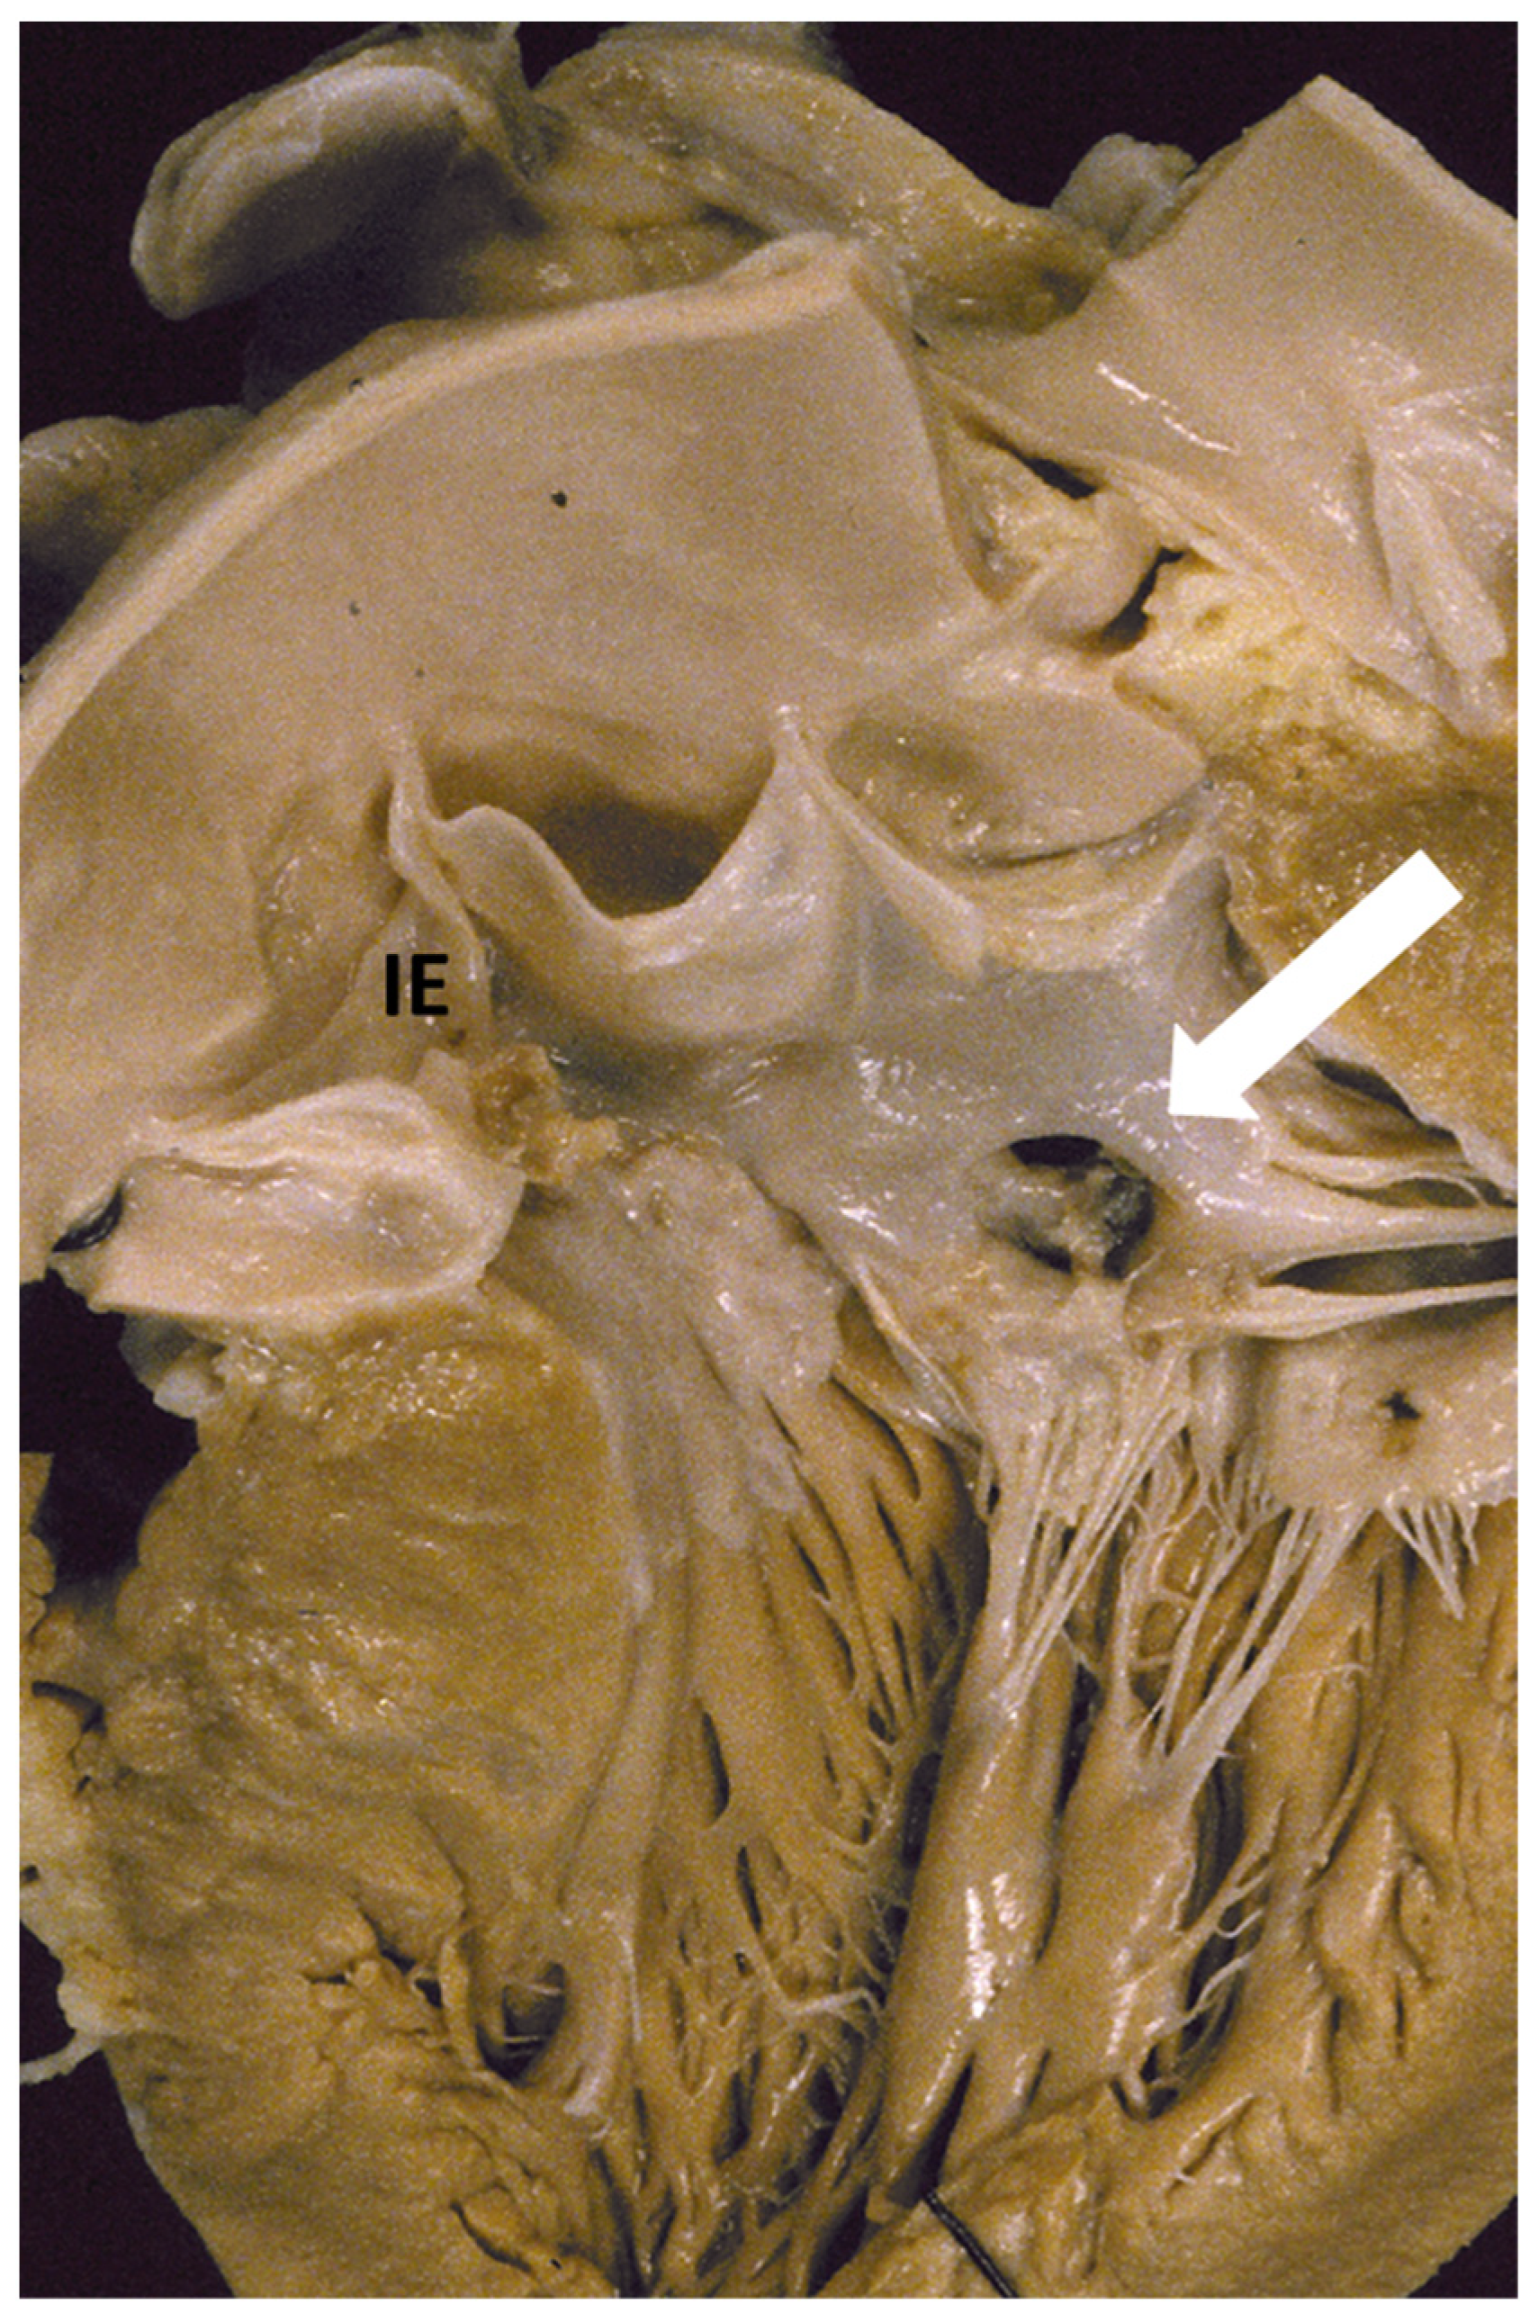

1. The Pathology Spectrum of Hypertrophic Cardiomyopathy

- Angelini, A.; Calzolari, V.; Thiene, G.; Boffa, G.M.; Valente, M.; Daliento, L.; Basso, C.; Calabrese, F.; Razzolini, R.; Livi, U.; et al. Morphologic spectrum of primary restrictive cardiomyopathy. Am. J. Cardiol. 1997, 80, 1046–1050. [Google Scholar] [CrossRef]